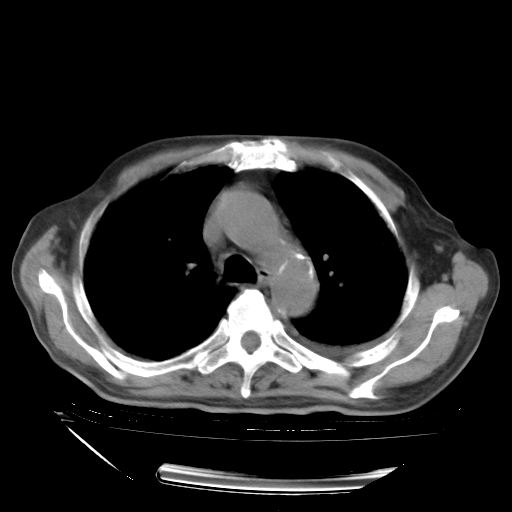

甲强龙80mg/日+抗结核治疗(异烟肼+利福霉素+乙胺丁醇)10天。复查肺部CT。

治疗10天肺部CT